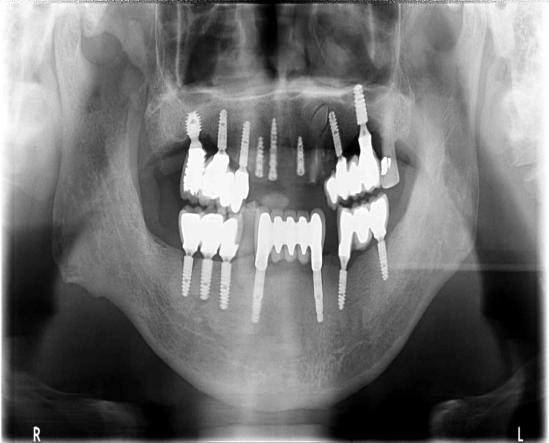

赖仁发教授经典案例:没有条件种,创造条件种

赖仁发教授经典案例:“沙漠”上创造出绿洲

种植体有长,有短,有细,有粗

因为种植牙,生活更美好

“愿每个缺牙老人都能吃、能喝、能咬、能唱!”这是赖仁发教授一直在力行的独到理念。种植牙的品质和效果是考核种植牙医生的关键要素,赖仁发教授这样说也是这样做的,工作中,他不仅身体力行践行严格的医疗管理理念,而且还严格要求整个医疗团队,暨南大学附属一院穗华口腔医院种出来的每颗牙都经得起时间的考验,才能获得越来越多的市民信赖。